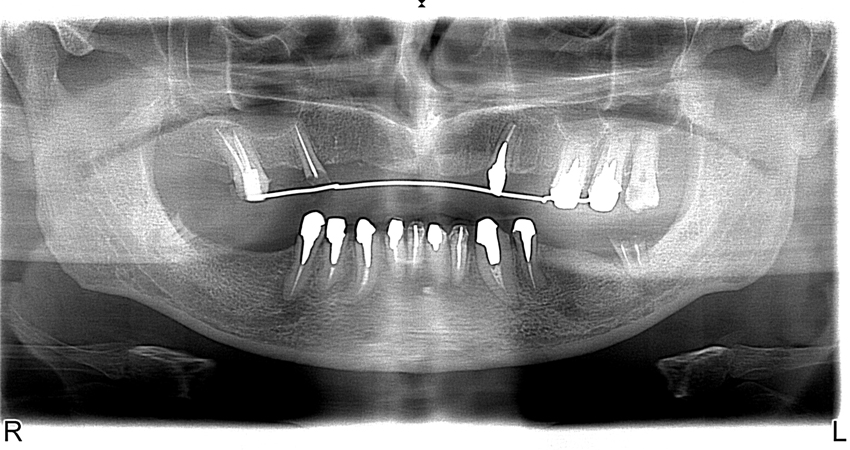

Pavel Kuts – Candidate of Medicine, Assistant Professor of Chair of Prosthetic Dentistry of the National Medical University named after A.A. Bogomolets. Honoured Doctor of Ukraine. Author and co-author of 43 published works in professional editions of the Highest Attestation Board of Ukraine, holder of 5 Patents and Certificates of Authorships. Ukraine A 36-year-old patient turned to the clinic with the complaints of absence of teeth and impaired chewing function.

Removal of 15, 23, 31, 32, 38, 41, 42, 48 teeth and curettage of alveolar sockets were performed under infiltration anesthesia. The mucous membrane was cut along the alveolar crest in the area of 16, 14, 12, 22, 25, 36, 37, 46 and 47 teeth. Exfoliation of periosteal mucosal graft. Formation of bone bed. Placement of Alpha Dent Implants in the area of 12, 14, 16, 22, 25, 36, 37, 46 and 47 teeth (Photo 5). The implants are covered with screw-type plug. Suture of mucous membrane. Adjustment of temporary removable dental prosthesis. Administrations: antibiotic therapy, removal of stitches in seven days.